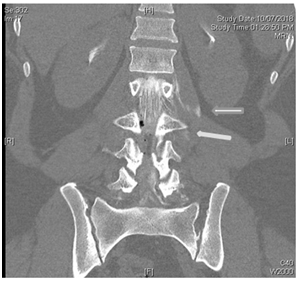

L 1/2 nerve root sleeve demonstrates bilateral small Tarlov’s cysts, the cyst on the left measures up to 4mm in diameter; the right measures up to 2.5mm in diameter; see Figures 7a & 7b.

Figure 7a & 7b Myelogram: Extravasation of contrast into the paravertebral soft tissue around the left lumbar 2/3 Tarlov cyst suggesting a CSF leak at this level.

In the dorsal and lumbar spine several other levels of nerve root Tarlov cysts are identified: none of these described Tarlov cysts show any extravasation into the surrounding soft tissues. 20ml of fresh blood was injected into the epidural space immediately after instillation of contrast into the CSF space. Initially the patient was pain free but required a second patch 1 week later due to return of symptoms.